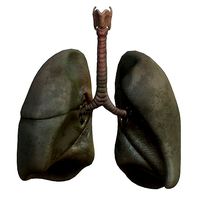

Lungs Smoker

...respiratory system lungs bronchi trachea larynx lobe osphagus epiglottis thorax ...

Lungs Human Smoker vs Non Smoker

...respiratory system lungs bronchi trachea larynx lobe osphagus epiglottis thorax ...